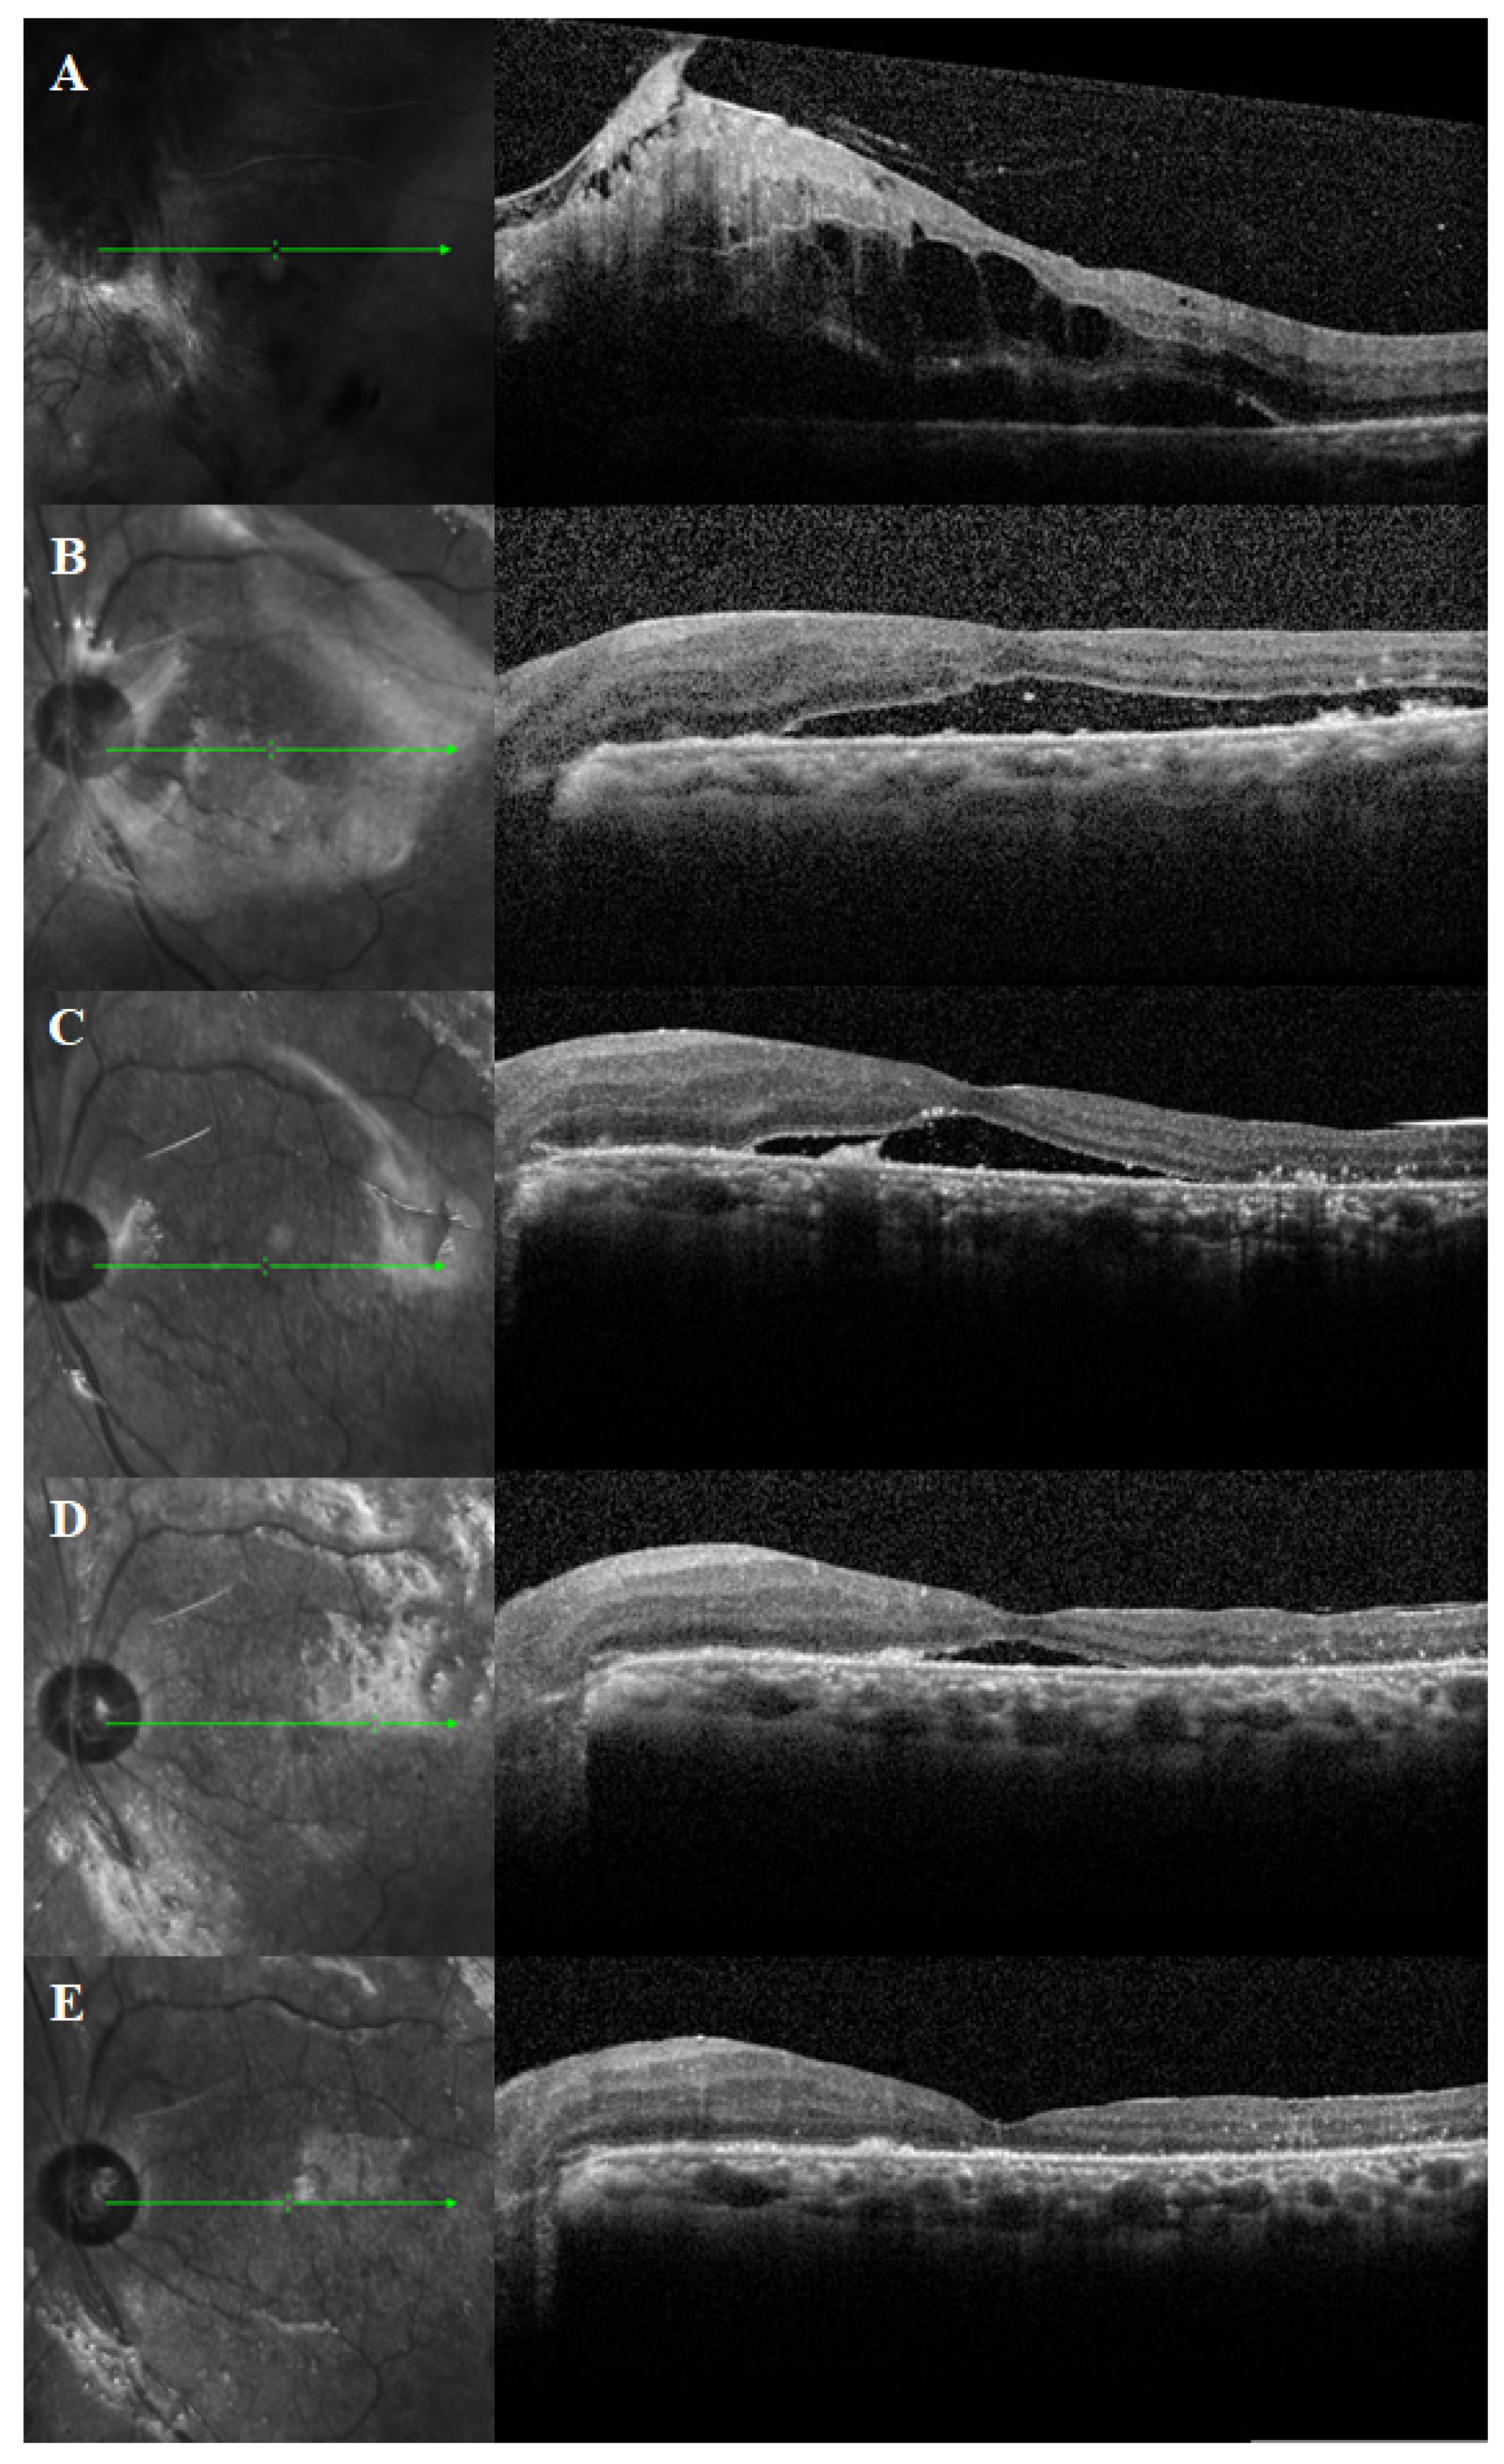

3.2. Duration of PSF and SRFH

3.3. Best-Corrected Visual Acuity